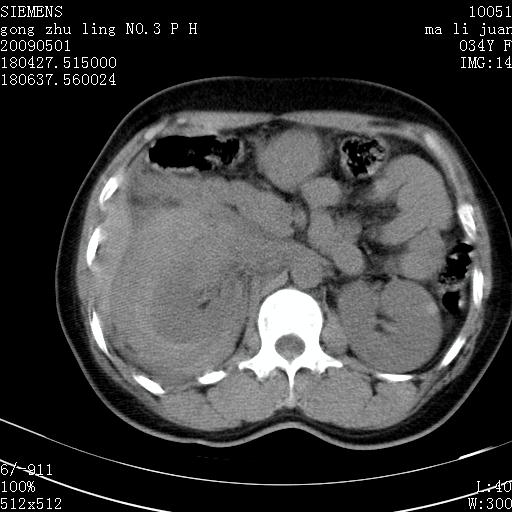

标题: CT19733:右肾碎裂

青年女性,骑摩托车摔伤。

右肾碎裂伤,包膜下血肿。

术中仅见右肾碎裂,肾蒂血管未见断裂。